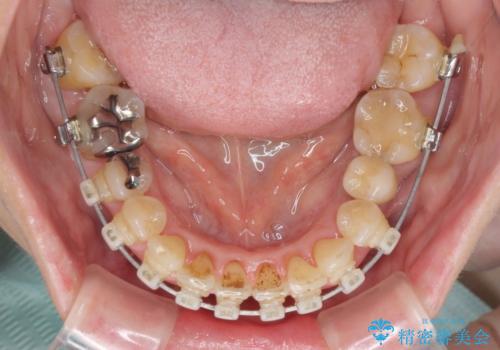

- 矯正装置

- クリアブラケット

- 近医にてインプラント治療を行った後に矯正治療を希望され、来院された患者様です。

口元の突出感とデコボコが気になっているとのことでしたが、インプラントが既に3本埋入されていたため、抜歯矯正による口元を引っ込めることができない状況でした。

近医での歯周病治療の影響でブラックトライアングルが発現していたため、IPR(歯と歯の間を削る)で隙間を改善しつつ、インプラントを固定源に歯列全体を後方へ移動させることとしました。